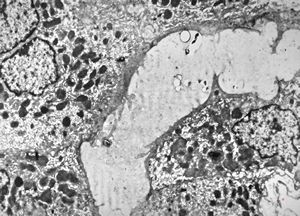

F,33y. | "ground glass" hepatocyte … filamentous inclusions ofhepatitis B surface antigen(HBsA)